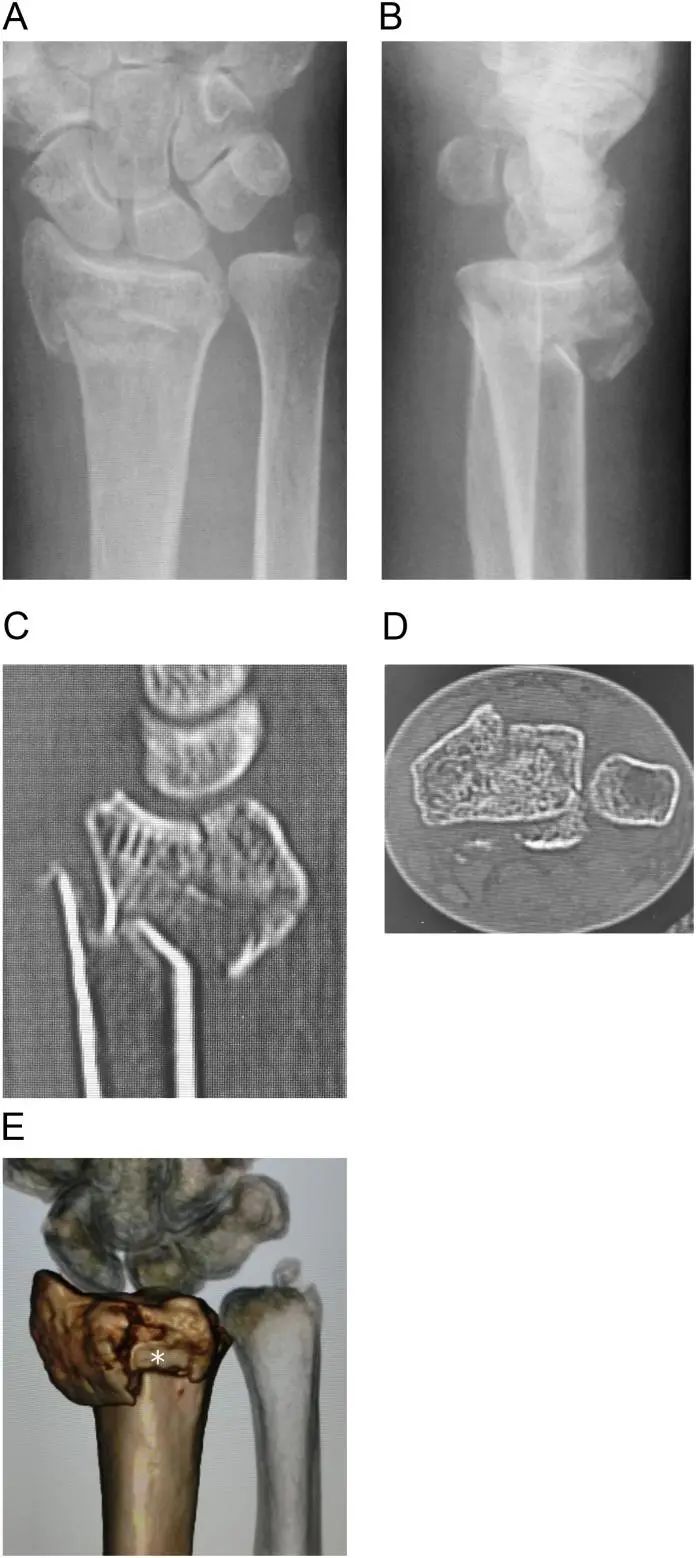

Le cas était une femme de 67 ans avec un diagnostic de fracture intra-articulaire instable du radius distal avec une fracture médiale dorsale droite (Figure 1A-E).Aucun antécédent de tabagisme, de diabète ou de consommation d'alcool.Peut marcher sans déambulateur.

figure 1. L'imagerie préopératoire a montré une fracture intra-articulaire comminutive du radius distal.

A et B : Radiographies préopératoires,

C et D : vues sagittale et axiale des images de tomodensitométrie,

E : image de tomodensitométrie 3D.Des fragments de facettes lunaires médianes dorsales et des fragments apicaux dorsaux (astérisques blancs) sont visibles.